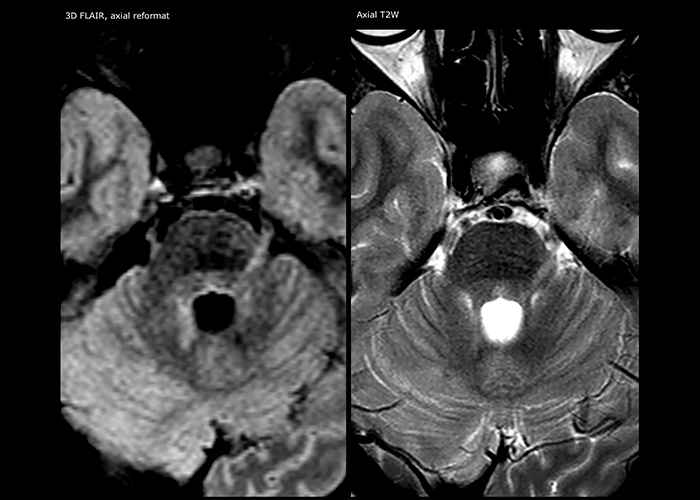

Imaging MS in brain

For MS imaging in the brain, Dr. Savatovsky uses 3D FLAIR as the basic sequence to visualize the lesions and assess the situation and lesion load. “We count the lesions in each location to determine if the criteria of the disease are fulfilled. We use a T2-weighted sequence because our neurologists are used to it. We compare the lesion load on FLAIR with a 3D T1 post-contrast sequence to help us determine whether lesions are old or new. We typically administer the contrast before the patient enters the machine because it shortens the examination time and allows to visualize active lesions that tend to be more visible after several minutes. When a differential diagnosis is difficult, we add sequences such as susceptibility imaging, because some focal MS lesions have a small vein in the center[3].”